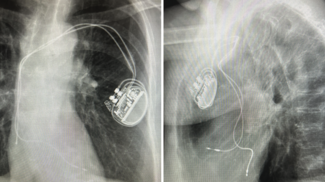

Sumit Verma, MD, FHRS, discusses components of a successful lead extraction program, including best practices for the initial consultation, managing traction and countertraction, and outcome transparency.